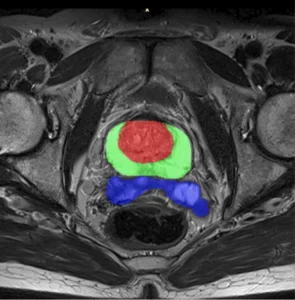

The crux of converting raw DICOM images into a surgically useful AI is medical image segmentation. This is where raw pixels transformed into anatomical reality.

For surgical planning AI, accurate segmentation not a luxury; it is the fundamental prerequisite. If an AI is tasked with delineating a tumor for resection, a 2 mm error in boundary definition could lead to incomplete resection (endangering the patient) or excessive tissue loss (resulting in functional deficit).

Ans: Inaccurate segmentation creates “geometric noise.” A 1 mm deviation in 2D contouring can result in a 3–5% volumetric error in 3D models. For orthopedic or cranial guides, this leads to poor mechanical fit, potentially causing intra-operative misalignment or hardware failure.